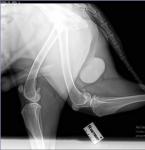

Начну с того, что не исключаю у Вашего пса дисплазию тазобедренных суставов. Думаю, что это она явилась причиной "шаркающей" походки с детства. Но в истории этой болезни она, по всей видимости, участия не принимает. Если Вы сделаете снимки суставов, то сразу выявите это заболевание. Думаю, тот факт, что собака плохо передвигалась, не связан с процессом в суставах, а с ухудшением общего состояния вследствие интоксикации, вызванной инфекционным процессом в предстательной железе. При гнойных процессах в организме животных их состояние быстро и значительно ухудшается. О происхождении абсцесса в простате ничего не могу сказать, это вопрос к ветеринарной медицине.